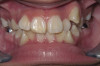

Cosmetic